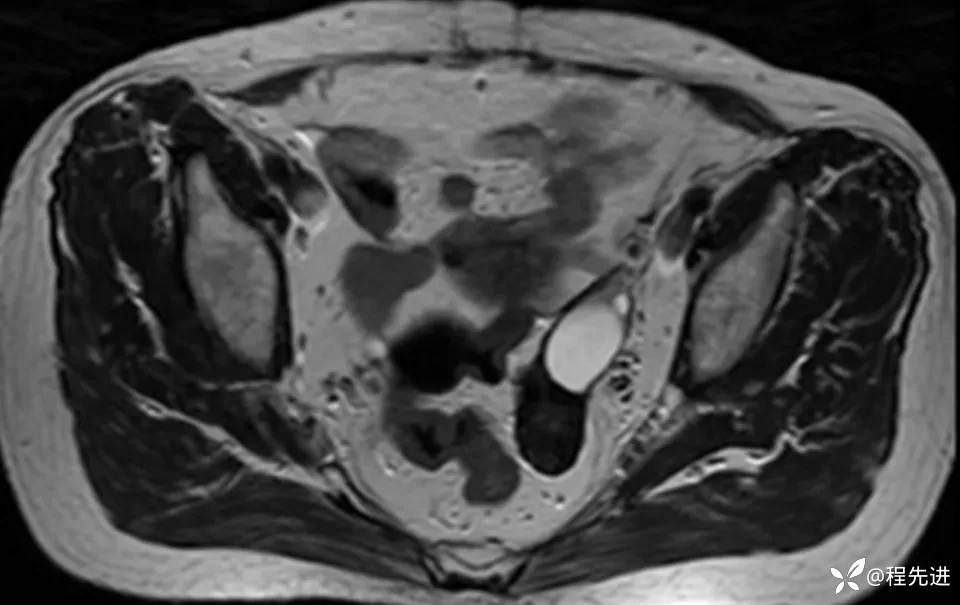

患者性别:女

患者年龄:60岁

简要病史:诊断乙状结肠癌术前常规检查发现

MRI平扫+增强: